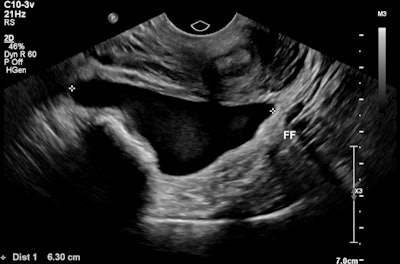

A 32-year-old female presented with severe constant left lower abdominal pain, per vaginal spotting and nausea. A pelvic ultrasound performed at six weeks' gestation demonstrated a viable intrauterine gestation and a small perigestational hematoma. A heterogeneous mass was noted abutting the left ovary. It featured peripheral vascularity, but no internal vascularity. There was small-volume pelvic free fluid with low-level internal echoes consistent with hemoperitoneum (see three images below).

Pelvic free fluid with low-level internal echoes consistent with hemoperitoneum.The patient was given a preliminary diagnosis of a hemorrhagic corpus luteal cyst. Heterotopic pregnancy was initially considered but thought less likely. The treating team opted for conservative management with a view to perform short-term follow-up ultrasound. Follow-up imaging two days later demonstrated a persistent left adnexal mass with interval increase in hemoperitoneum volume. The mass was seen to move separately to the left ovary on transvaginal/abdominal palpation maneuvers.

Moderate free fluid with low level echoes within the pouch of Douglas consistent with hemoperitoneum.